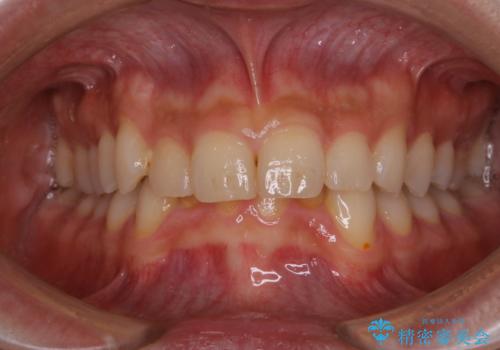

- 歯科でのクリーニングが5・6年ぶりで、全体をきれいにしたいとのことで来院されました。PMTC60分コースを行いました。

PMTCとは「Professional Mechanical Tooth Cleaning」の略で、専用の機器を使った歯のクリーニングです。

審美的面だけではなく、歯周病や虫歯・口臭などのリスクを予防することができます。